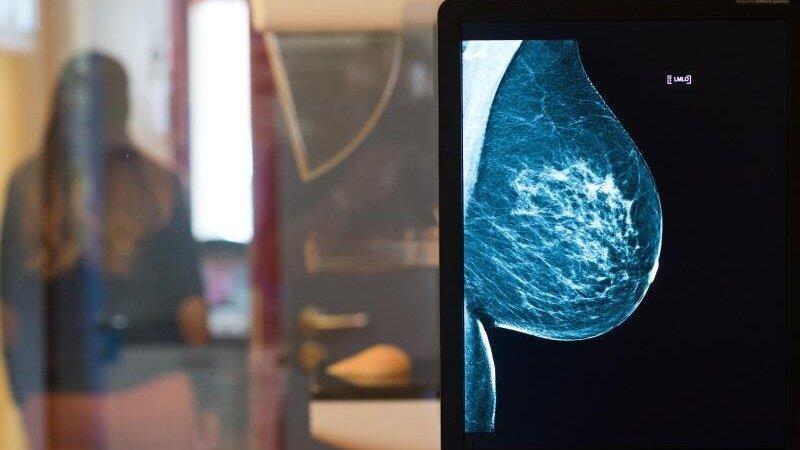

Röntgenbild eines Mammographie-Screening-Programms: In Straubing ist die Untersuchung in der Woche vom 25. bis 29. wieder möglich. (Symbolbild)

Frauen können in Straubing wieder zur Brustkrebs-Früherkennung gehen. Unter besonderer Berücksichtigung der vom Robert-Koch-Institut empfohlenen Hygienevorkehrungen werden im MVZ am Theresientor wieder Screenings zur Brustkrebs-Früherkennung durchgeführt, heißt es in einer Mitteilung im Auftrag des Mammographie-Screenings Niederbayern.

"Brustkrebs-Früherkennung ist wichtig, deshalb führen wir die Untersuchungen jetzt unter den gebotenen Vorsichtsmaßnahmen weiter. Dazu gehört auch, dass jeder eine Maske trägt", erklärt Dr. Margarete Murauer und betont, dass jede Frau eine eigene Maske mitbringen muss und den Termin verschieben soll, wenn grippeähnliche Symptome auftreten. Dr. Murauer ist zusammen mit Dr. Andrea Simkova von "Radio-Log" in Passau für die Umsetzung des Mammographie-Screenings in Niederbayern verantwortlich.